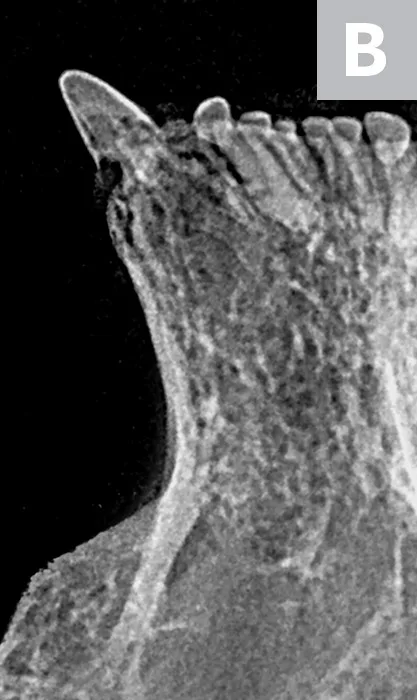

Tooth resorption type is determined via intraoral radiography based on root opacity and periodontal ligament space (see Types of Tooth Resorption Based on Radiographic Appearance and Figure 2).

Radiograph of a left mandibular molar tooth in a cat with Type 1 resorption (A) in which focal or multifocal radiolucency can be seen with otherwise normal radiopacity and normal periodontal ligament space. Radiograph of mandibular incisors and canine teeth in a cat with Type 2 resorption (B; white arrow) in which narrowing or disappearance of periodontal ligament space is present in at least some areas, and part of the tooth demonstrates decreased radiopacity. Radiograph of the right maxillary third and fourth premolars in a cat with Type 3 resorption (C); the third premolar features Type 1 resorption of the mesial root (arrowhead) and Type 2 resorption of the distal root (dashed arrow) with exposure to the oral cavity.